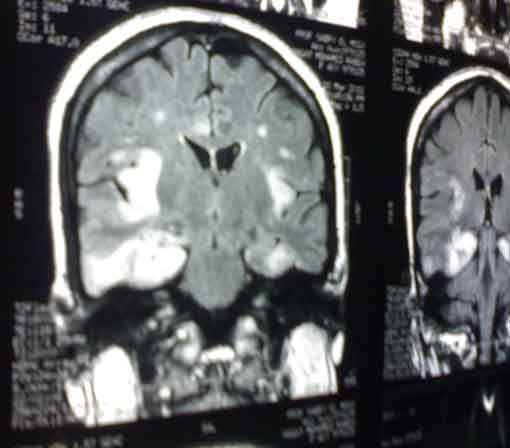

MRI for a female patient aged 41 who presented in a state of disturbed

conscious level which preceded days before by fever, headache,

hallucinations, behavior changes and weakness of lower limbs.

What is the diagnosis?

It is a case of "Herpes Encephalitis". Note

the obvious temporal lobe involvement.